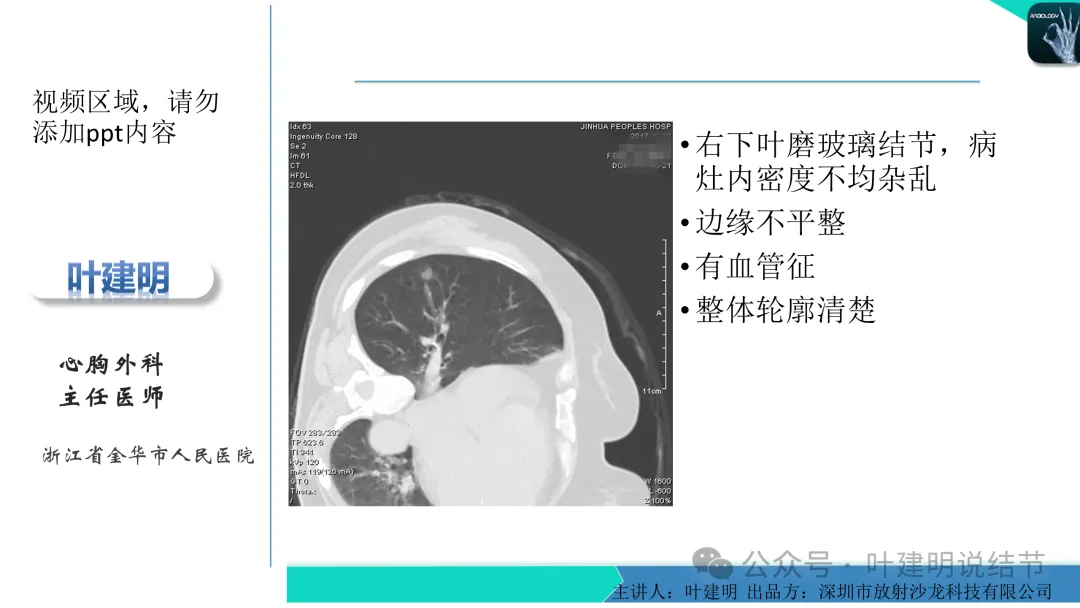

当地说考虑微浸润性腺癌的左下主病灶影像连续层面展示:

某省胸科医院医生会诊后给出的意见是:左下肺后基底段(结节)达Lung-rads4B类,微浸润性腺癌可能,建议手术干预。签名的是B医生,后面给出了周一A主任肺结节门诊,周四B主任门诊。大概是团队成员,A医生是著名大咖,B医生是团队骨干成员!

这个病灶会是微浸润性腺癌吗?当然没有病理诊断,我也不能说百分之百必不会,但这样的病灶已经风险大到必得尽快手术切除干预了吗?显然还早着呢:1、影像不是典型的结节状;2、边缘与轮廓模糊不清;3、灶内似有细支气管扩张(更容易是细支气管扩张伴少许周围炎或肺泡上皮增生);4、血管邻近走但无牵拉影响;5、没有实性成分,没有锐利毛刺,没有胸膜牵拉,没有血管进入,没有任何倾向风险性高的影像特点。我一直强调:肺结节是否要干预处理,不要纠结于最后病理是什么,而要看风险高低;而风险高低的最重要术前判断依据一是随访有无进展,二是有没有实性成分。只要没有肉眼可见的影像上的实性成分,风险就是低的!何况病理也是人看的,原位还是微浸润,不典型增生还是原位有时也在一念之间。